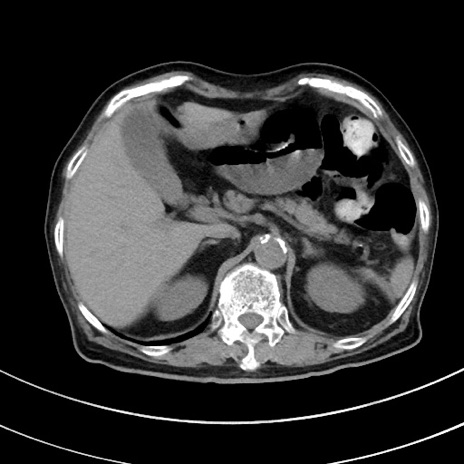

冠状断像

【症例】70歳代 女性

【主訴】心窩部痛

【現病歴】延髄病変の精査・加療にて神経内科入院中。本日より心窩部痛あり。

【既往歴】虫垂炎

【身体所見】右下腹部を中心に圧痛と反跳痛あり。

【データ】WBC 10900、CRP 0.02